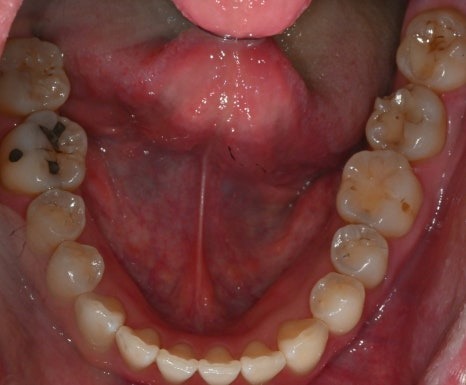

치료 전

치료 후

· 60대 남성 환자

기존 보철물 주변 충치와 다수의 어금니 손상으로 내원

→ 수면치료를 통해 하루에

충치치료와 임플란트 수술까지 병행